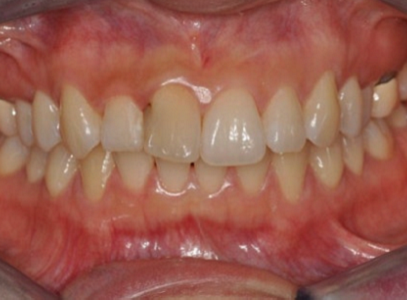

케이스 1. 정면에서는 앞니만 삐뚤어 보이지만, 옆모습과 교합을 보면?

하지만 옆에서 치아와 얼굴 측면을 함께 보면,

위 앞니가 전체적으로 앞으로 많이 나와 있는 상태(돌출) 이고

오른쪽과 왼쪽의 치아 맞물리는 위치도 서로 다릅니다.

양쪽 모두에서 윗니가 전반적으로 앞으로 나와 있는 교합입니다.

이런 경우, 단순히 윗니만 부분교정을 하게 되면,

위·아래 앞니 사이의 앞뒤 간격이 더 벌어질 수 있고,

그로 인해 기능적인 문제(저작, 발음, 교합 안정성 등)가 생길 수 있으며,

사진상으로는

앞니 배열이 가지런해지고

정면에서 보았을 때 인상이 더 단정해진 것처럼 보일 수 있습니다.

그러나 의료진의 입장에서는,

“당장은 보기 좋을 수 있지만,장기적인 안정성과 교합 기능 측면에서는 염려되는 부분이 남아 있다”

라고 평가할 수밖에 없는 케이스입니다.